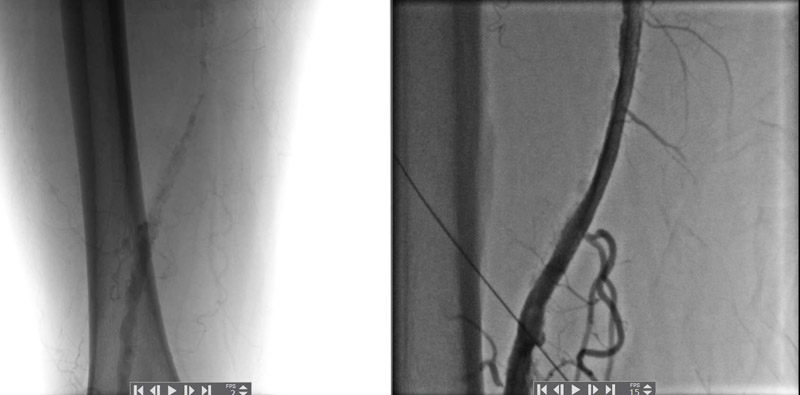

Результаты артериральных реконструкций

До и После